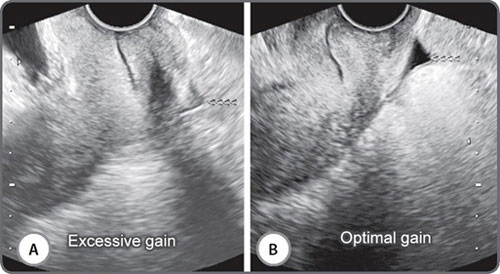

Adjusting gain alters how the transducer perceives returning echoes. Increasing the gain brightens the display of the returning echo information. Gain may be adjusted for the entire image (overall gain), or at depth, known as time-gain compensation (TGC).3 Excessive gain makes the image too bright, and too little gain makes it dark (Figs 2A and B). Excessive gain can make the picture bright with noise. This can obscure fluid echoes (Figs 3A and B). Too little gain may create fluid echoes where no fluid exists (Figs 4A and B). Many currently available medium and high-end units now have a one-touch image optimization button that works automatically to fix the gain in an image.

Figs 2A and B: Excessive gain obscures textural detail. There is excessive gain in the image on the left (A) and the texture and margins of the endometrium are indistinct. The image on the right (B) has optimal gain. The triple layered proliferative phase morphology is distinct and no focal lesion is evident

Figs 3A and B: Excessive gain can obscure fluid echoes. The image on the right (B) was obtained at optimal gain settings and shows a small quantity of free fluid (<<<<) in the pouch of Douglas. The image on the left (A) was obtained at high gain settings and the fluid (<<<<) is largely obscured

Figs 4A and B: Inadequate gain can “create” fluid where none exists. In the image on the left (A); a large fluid collection is evident in the right adnexa. Increasing the gain [right (B)] reveals an ovary with three antral follicles